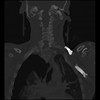

23 ANGIO,CE,Cor-MIP,5.000,ANGIO,Cor-MIP,